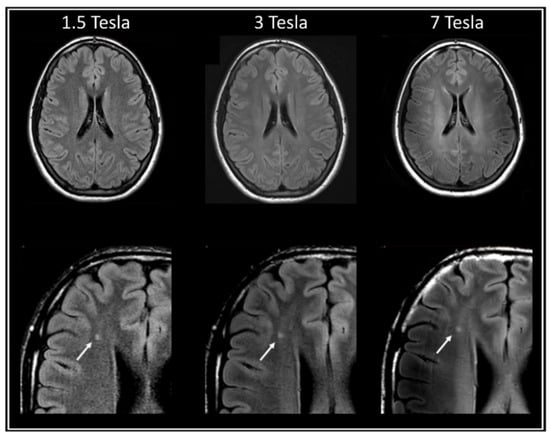

- Trattnig, S.; Springer, E.; Bogner, W.; Hangel, G.; Strasser, B.; Dymerska, B.; Cardoso, P.L.; Robinson, S.D. Key clinical benefits of neuroimaging at, 7.T. Neuroimage 2018, 168, 477–489. [Google Scholar] [CrossRef]

- Zwanenburg, J.J.M.; Hendrikse, J.; Visser, F.; Takahara, T.; Luijten, P.R. Fluid attenuated inversion recovery (FLAIR) MRI at 7.0 Tesla: Comparison with 1.5 and 3.0 Tesla. Eur. Radiol. 2010, 20, 915–922. [Google Scholar] [CrossRef] [PubMed]